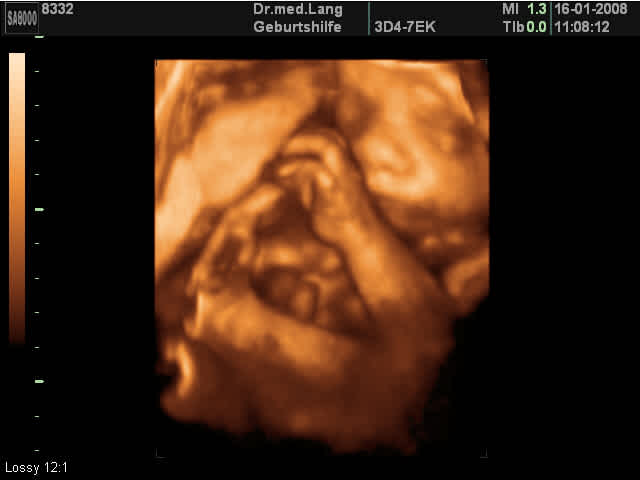

Organscreening Ein Organscreening ist eine Ergänzung Ihrer MutterKindPass Untersuchungen Im Rahmen dieser zusätzlichen Ultraschalluntersuchung werden viele Details beim Kind dargestellt Besonders werden das Gesicht, das Herz und das Gehirn und die gesamte Anatomie des Kindes begutachtet Die Untersuchung erfolgt nach internationalen Standards und Richtlinien und erfordert eine fundierte. Kann man 3D Ultraschall in der 26 ssw machen?. Hier wird in der Regel ein 3DUltraschall eingesetzt SSW 26 SSW 27 SSW 28 SSW 29 SSW 30 SSW 31 SSW 32 SSW 33 SSW 34 SSW 35 SSW 36 SSW 37 SSW 38 SSW 39 SSW 40 SSW Vornamen für euer Baby Liste Die 0 beliebtesten Vornamen 21 in Deutschland für Mädchen und Jungen.

In der 26 Schwangerschaftswoche passiert Aufregendes im Leben des Fötus Seine Augen öffnen sich Die 26 SSW ist ein guter Zeitpunkt für einen 3DUltraschall, auch BabyTV genannt Bei. SSW das Gestationsalter um 4 e unterschätzt (3,7 mm Differenz im CRL), dafür in der 11–14 SSW um einen (0,8–1 mm) überschätzt Die aus dem Jahr 19 stammenden HadlockKurven unterschätzen das Gestationsalter in der 6 SSW um 3 e (2,7 mm) und überschätzen es in der 14 SSW um 2 e (4,8 mm). Antwort auf Gewicht Baby in der 26 ssw (253) Hallo, 1 in der 26SSW sollte das Gewicht zwischen Gramm liegen und der Mittelwert liegt hier bei 913 Gramm 2 mit 600 Gramm wäre das Gewicht also deutlich zu niedrig Jedoch ist es wichtig, zu wissen, dass es zu diesem frühen Schwangerschaftszeitpunkt bei der Berechnung über die Ultraschallsoftware noch größerer Fehler geben kann.

Oder ist das noch zu früh?. Das Baby in der 26 SSW In der 26 Schwangerschaftswoche misst das Baby in der ScheitelFersenLänge zwischen 34 und 36 Zentimeter Es wiegt jetzt etwa 750 bis 900 Gramm Nach wie vor ist es sehr beweglich Oft streckt es sich zu seiner vollen Länge Im Ultraschallbild zeigt sich oft ein kleiner Daumenlutscher das Baby bildet seine Reflexe. Ssw (26 Schwangerschaftswoche) ist das ungeborene Kind etwa 34 bis 36 cm groß und wiegt dabei ca 900 Gramm es ist weiterhin sehr beweglich und kann sich noch in voller Länge ausstrecken Wenn Ihr Gynäkologe jetzt einen Ultraschall durchführt, können Sie beobachten, wie Ihr Baby am Daumen lutscht.